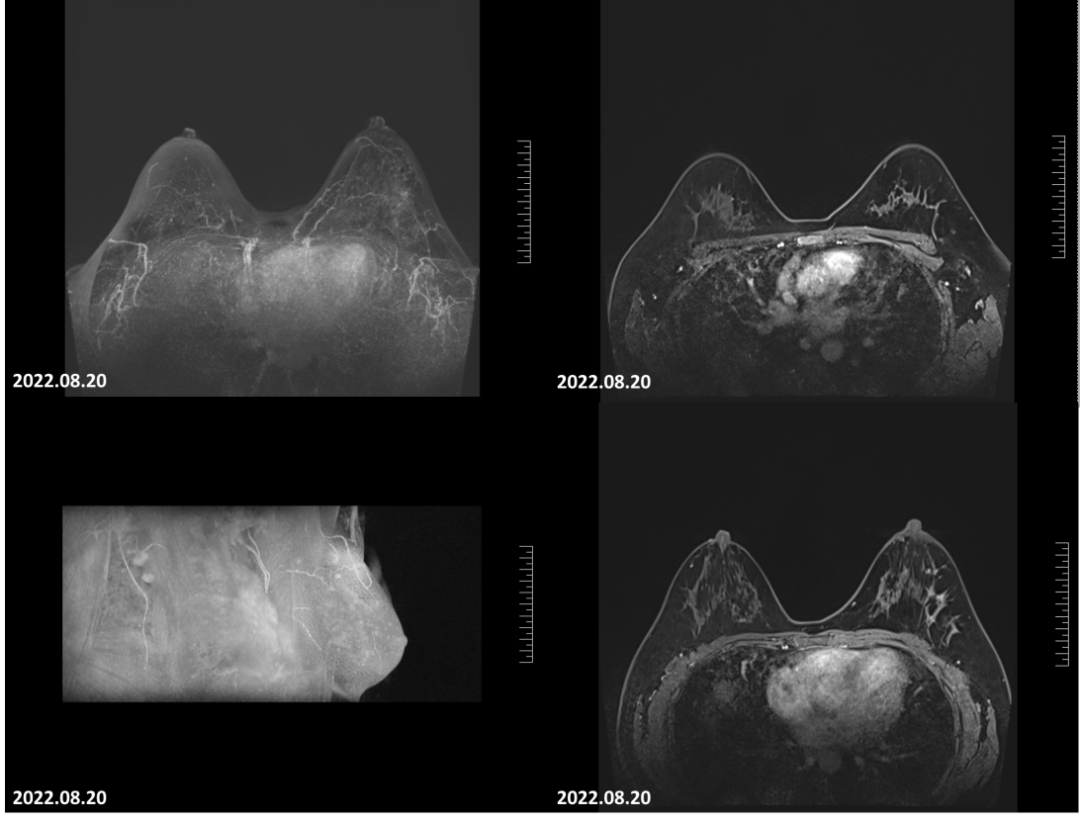

2022-08-20乳腺MRI报告:左乳上方可见点灶状强化,以左乳约3点钟方向稍明显,直径约4mm。大小约24mm×30mm×21mm(上下径×左右径×前后径),病变前缘距乳头约34mm,后缘距离胸壁约11mm。左侧腋窝淋巴结肿大,最大直径约7mm。

图6.4疗程后患者左乳肿物轮廓不明显,左乳肿物及左腋窝淋巴结均无明显增强。

2022-08-20乳腺超声:左乳可见多处低回声结节,较大者位于12点钟,大小约11mm×7mm×11mm,距体表10mm,距乳头35mm,形态不规则,边缘成角,内回声不均匀。CDFI:内可及点状血流信号。左侧腋窝可见数个淋巴结回声,髓质消失,较大者大小约12mm×8mm。CDFI:内可见点状血流信号。右侧腋窝及双侧锁骨上窝未见明显肿大淋巴结。

图8 4疗程后,患者左乳肿物核心基本消失,淋巴结缩小至正常大小。

因4个周期治疗后,乳腺MRI及彩超显示靶病灶核心已不明显,临床疗效评估为CR,继续治疗缺乏可对比的靶病灶评估疗效,进行多学科会诊后,建议患者进行手术,患者同意手术治疗。